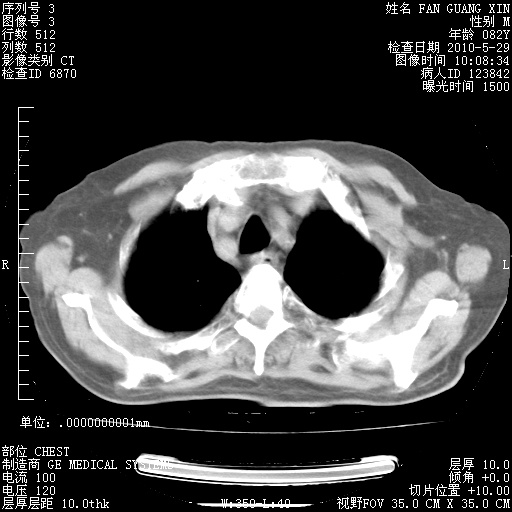

治疗3周后的肺部CT纵隔窗

再治疗10天后的肺部CT

再治疗10天后的肺部CT 纵膈窗

阅读此次胸部CT,肺间质渗出性改变较入院时有吸收。目前从体温、白细胞、中性分叶明显增高,肯定存在细菌感染(发生医院感染哦,若无消化道及泌尿系统等感染的依据,肺部感染可能大)。若你院头孢哌酮舒巴坦钠耐药率较高,同意你的方案,若48小时体温仍高,可考虑使用碳青霉稀类抗菌药物,同时可予超声雾化、注意滴数时加大液体量。白蛋白33.30g/L较低哦,需加强营养等支持治疗。